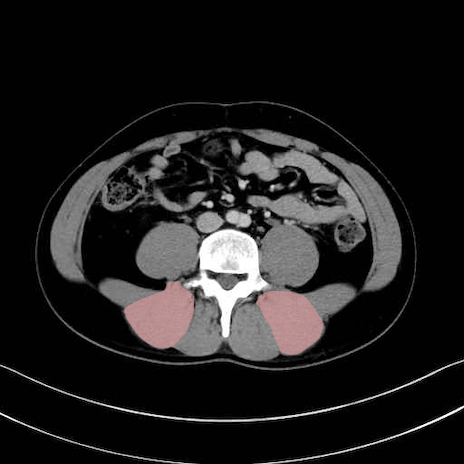

脊柱起立筋 (Erector spinae)

多裂筋 (Multifidus)